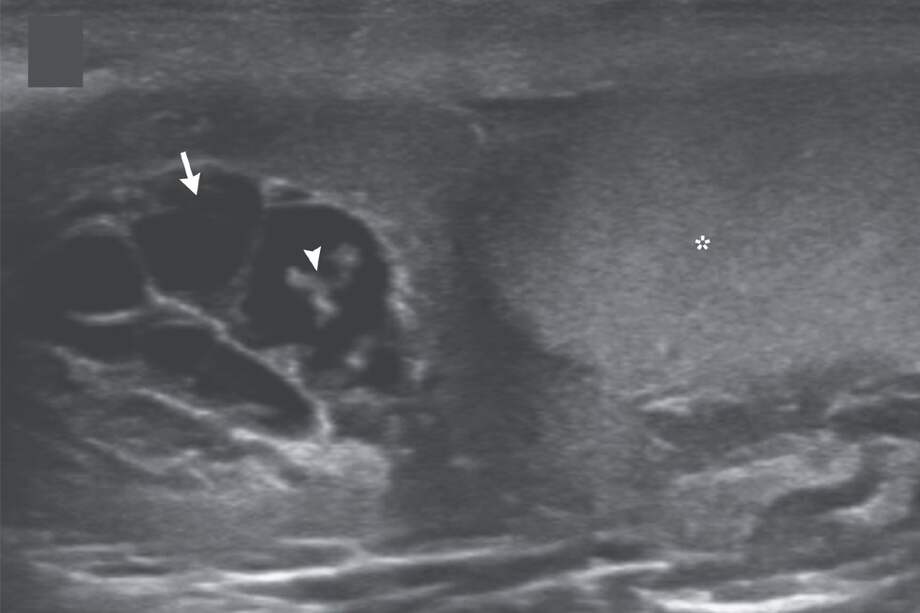

Una vez en urgencias, los médicos le tomaron una serie de ecografías para determinar la causa de sus síntomas. Pero, al recibir los resultados, se llevaron una sorpresa: detectaron múltiples gusanos parásitos dentro de la piel de su escroto.

En la investigación, los médicos explicaron que encontraron a los gusanos ‘bailando’, lo que “representa las ondulaciones de los gusanos vivos. Ellos han migrado a los canales linfáticos, causando dilatación y disfunción de los canales”.